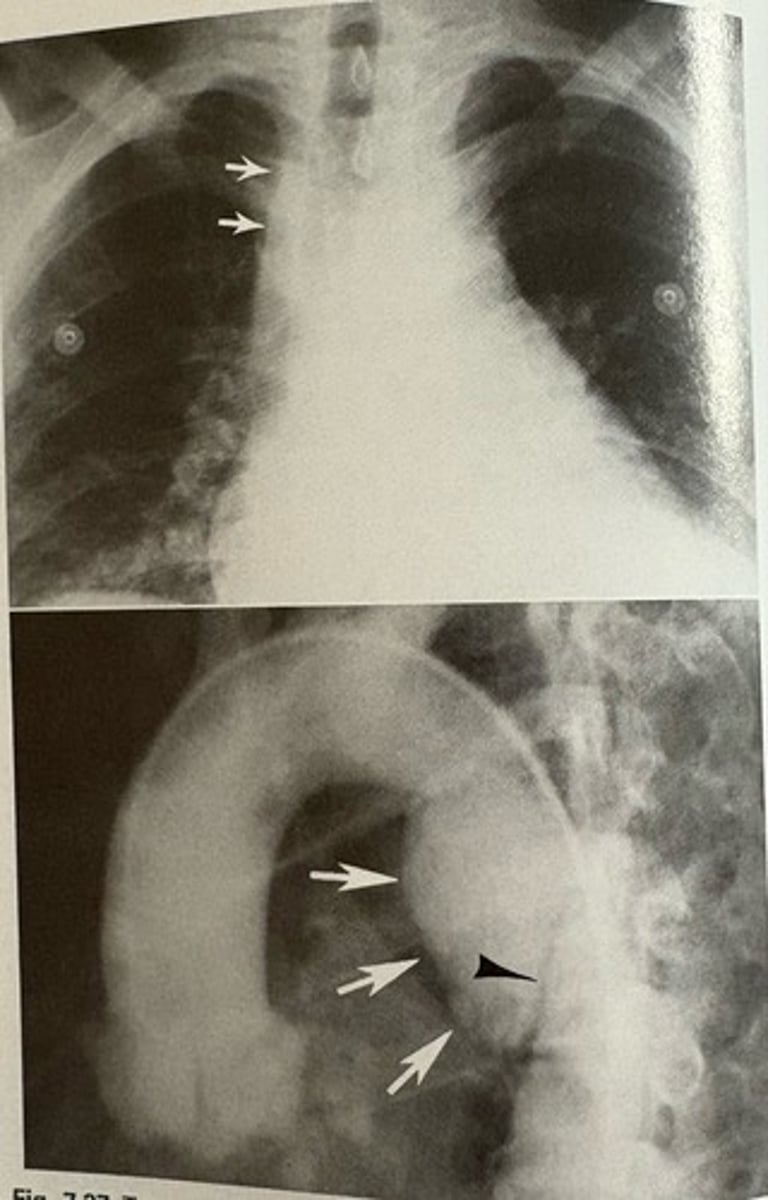

traumatic aneurysm of the aorta

what pathology is present?